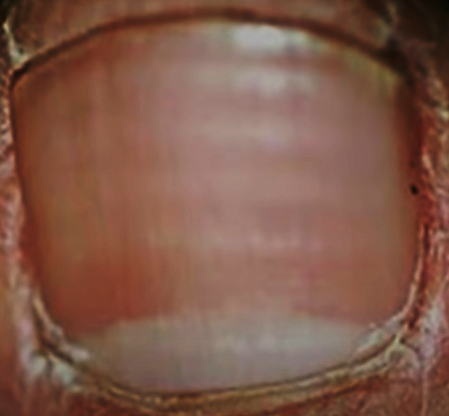

3. 속손톱이 없어지고 손톱판이 대부분 하얀색으로 변했다면?

테리손톱이라고도 한다. 희고 탁하게 보이며 손톱의 끝 부위 약 1 ~ 3mm만 붉거나 푸른빛을 띤다.

간경화 환자의 80%에서 관찰된다.

그 외에도 만성 울혈성 심부전, 당뇨병, 만성 콩팥병, 요독증 환자에게서 많이 관찰된다.